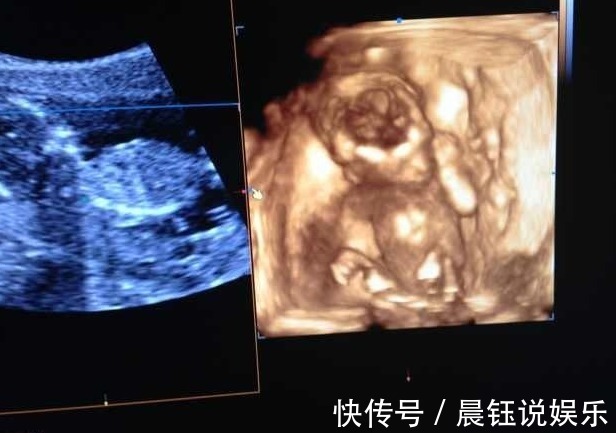

由于她的年纪小,怀孕后她并不知道,所以等到快三个月的时候她才反应过来,于是她要去做产检也是在怀孕3个月后去的。而第一次产检她婆婆就陪着她去,也怕她不懂所以陪着去,等到了医院后,医生就开始问了很多问题,因为医生想要了解孕妇的健康情况,也要根据这些情况来判断孕妇未来的一个生产方式等等!

一般一些丰富经验的医生就会问的比较细致,而且还会有一些很尴尬的问题。于是有的医生也会先把家人支开再问,避免引起不必要的事端。而洁儿运气也好,这个医生也是把她婆婆支开了,于是问他有没有做过流产,洁儿一听非常尴尬,脸瞬间就红了,然后她也如实的回答了,说有过一次!果不其然,像这样有经验的医生可能早就猜到了。其实她婆婆心里也明白,事后也一直想套话,但是洁儿也知道婆婆想知道,也没有被套话。

- 四维彩超|孕期最关键的4次产检,就算再忙,宝爸也要陪孕妈一起